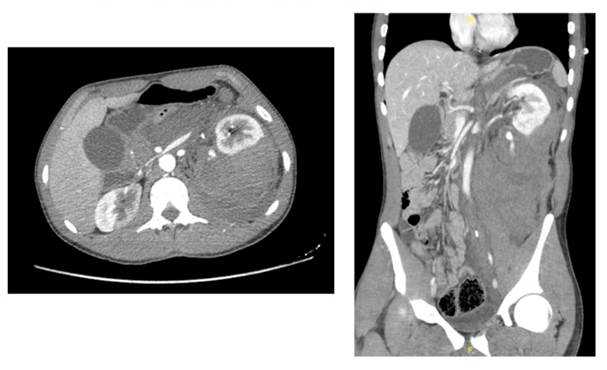

A 19-years-old female with no medical history, presented to the ER with abdominal contusion and pain after falling from an e-scooter while riding it at 30km/h under alcohol influence. Physical exam showed many bruises, low consciousness, a bigger bruise in the right flank and significant pain with the palpation on an unstable patient. The CT scan showed liver lacerations and a shattered right kidney (Figure 11, 12 & 13) that ended with an urgent nephrectomy (Figure 14). The patient had a postoperative recovery with no incidences and went home with a normal GFR and hemoglobin, being followed afterwards with an ambulatory CT scan and renal function monitoring.

Axial, coronal and sagittal planes. Liver lacerations and a shattered right kidney.

Figure 11, 12 & 13 Contrasted abdominopelvic CT scan